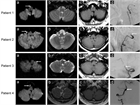

1. 急性期の血管内治療について、解離による頭蓋外頸動脈狭窄とそこからの塞栓による頭蓋内動脈閉塞については血栓回収療法の有用性が示されてきている。

1. MRA、CTAによって解離の特徴的な所見を見逃さないようにする。